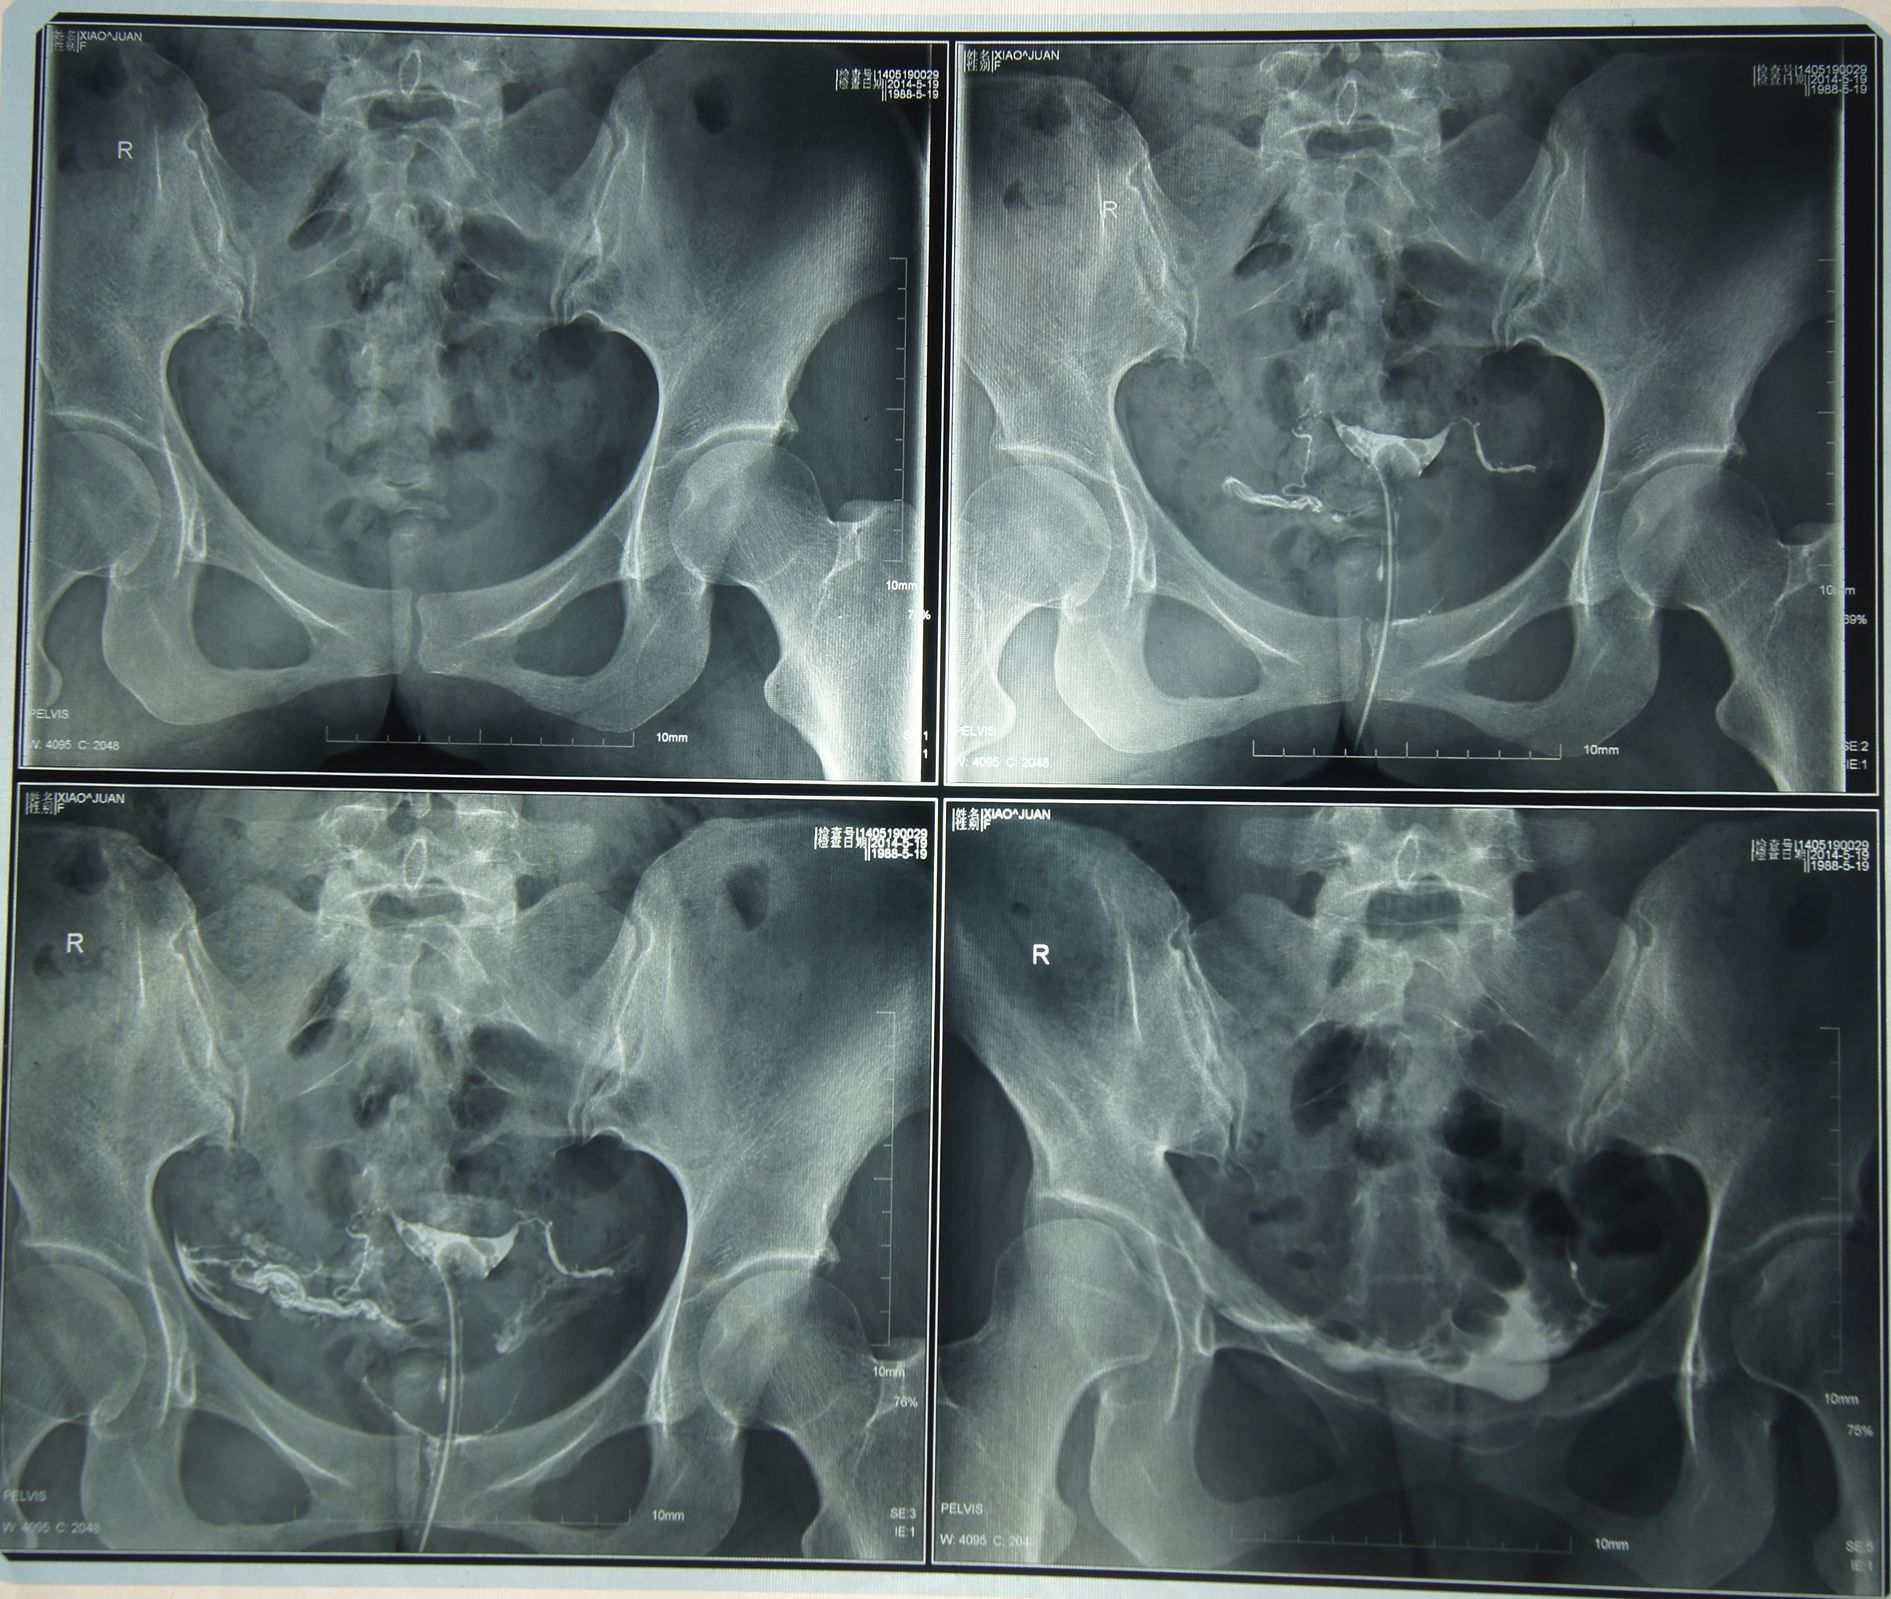

主是宫外孕,本人有两次宫外孕,1次人流,这造影人医说有侧输卵管堵塞,但我忘记是哪一侧了,医生建议我

做腹腔镜手术。我去年7月份宫外孕做一次腹腔镜手术,不知道是不是身体体质差的原因,做这次造影都晕过去了,所以不想在做,想问一下有医师对于我的情况,有没有更好的方法方式。

你好,输卵管分为间质部,峡部,壶腹部和伞端,输卵管间质部,峡部,是属于输卵管近端,输卵管壶腹部和伞端是属于输卵管远端。长约8~15cm。输卵管具有拾卵,输送精,卵,提供受精的场所,滋养受精卵和输送受精卵到达宫腔等功能,输卵管功能正常与否和输卵管平滑肌的蠕动,上皮纤毛的活动,输卵管的通畅以及输卵管液的...分泌密切相关,任何一方面异常都会导致不孕。建议你尽快治疗。